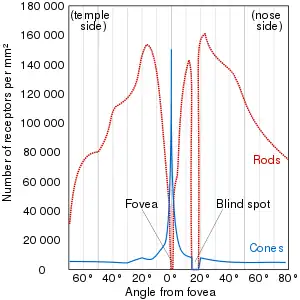

A blind spot, scotoma, is an obscuration of the visual field. A particular blind spot known as the physiological blind spot, "blind point", or punctum caecum in medical literature, is the place in the visual field that corresponds to the lack of light-detecting photoreceptor cells on the optic disc of the retina where the optic nerve passes through the optic disc.[2] Because there are no cells to detect light on the optic disc, the corresponding part of the field of vision is invisible. Processes in the brain interpolate the blind spot based on surrounding detail and information from the other eye, so it is not normally perceived.

The blind spot in humans is located about 12–15° temporally and 1.5° below the horizontal and is roughly 7.5° high and 5.5° wide.[3]

Night blind spot

It is estimated that once fully adapted to darkness, the rods are 10,000 times more sensitive to light than the cones, making them the primary receptors for night vision. Since the cones are concentrated near the fovea, the rods are also responsible for much of the peripheral vision. The concentration of cones in the fovea can make a night blind spot in the center of the field of vision.[4]